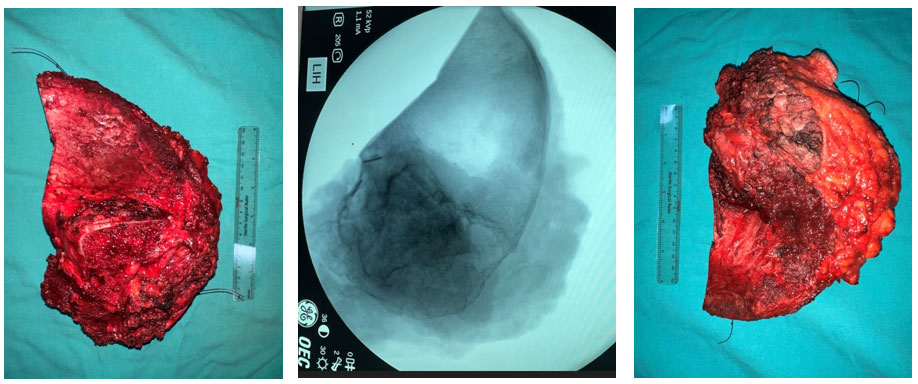

Ameliyat esnası: Çıkarılan tümör dokusunun klinik ve radyolojik görüntüsü